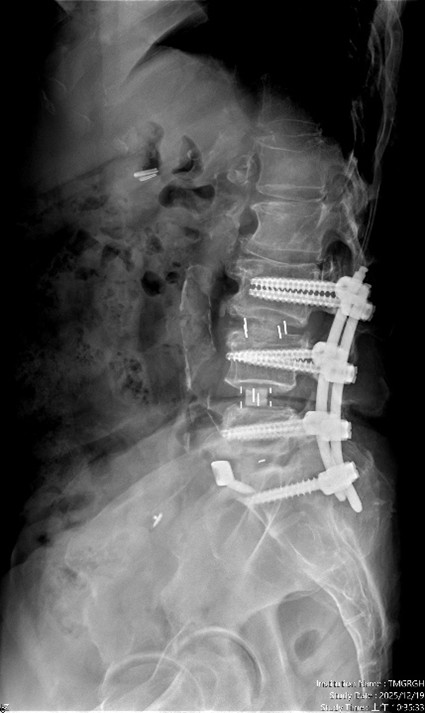

經 臺中市立老人復健綜合醫院 骨科部副部長 林琮凱 醫師 詳細檢查後,診斷為第三、四、五腰椎合併第一薦椎之多節段脊椎狹窄與神經壓迫。醫療團隊與病患及家屬充分溝通後,決定採用「電腦 3D 導航輔助之前位/前側位脊椎融合手術」,合併後方骨釘固定,一次完成多節段重建。術後病患神經症狀明顯改善,行走能力恢復,生活品質大幅提升。

【手術前及手術後】手術前有脊椎滑脫不穩定及脊椎狹窄造成神經壓迫(左圖)。手術後除了重建椎間高度,也將腰椎的生理曲線重建為較理想的前凸狀態(右圖)。官方提供